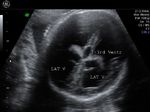

Ultrasound images of fetal Brain

Sonography in Dandy-Walker syndrome:

The above ultrasound images of fetal brain show hypoplastic cerebellum and absent vermis with enlarged 4th ventricle which is typical of Dandy-Walker malformation. Images courtesy of Dr. Gidda Ramaiah, India. (Note: click to view larger images).